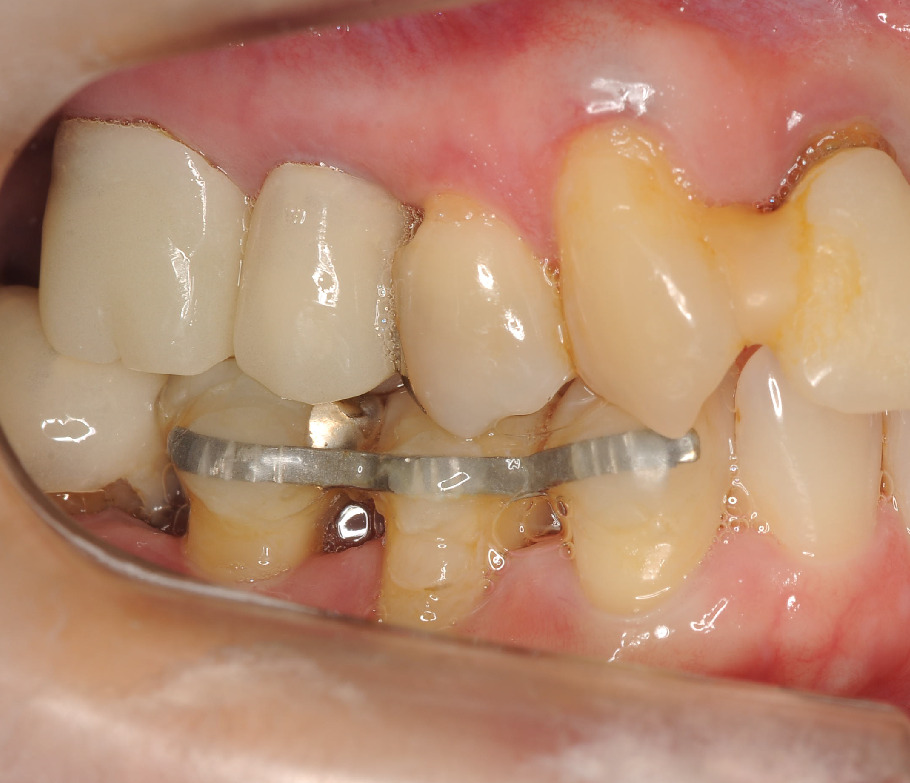

この方も、右下の歯がぐらつき、咬めない。。。との来院でした。

動揺が3度(上下運動します)でしたので、直ぐに応急処置でワイヤーで固定します。

レントゲンを見ると

とくに右下4番(一番右の歯)が根の先まで骨が溶けています。歯周ポケットは8mm